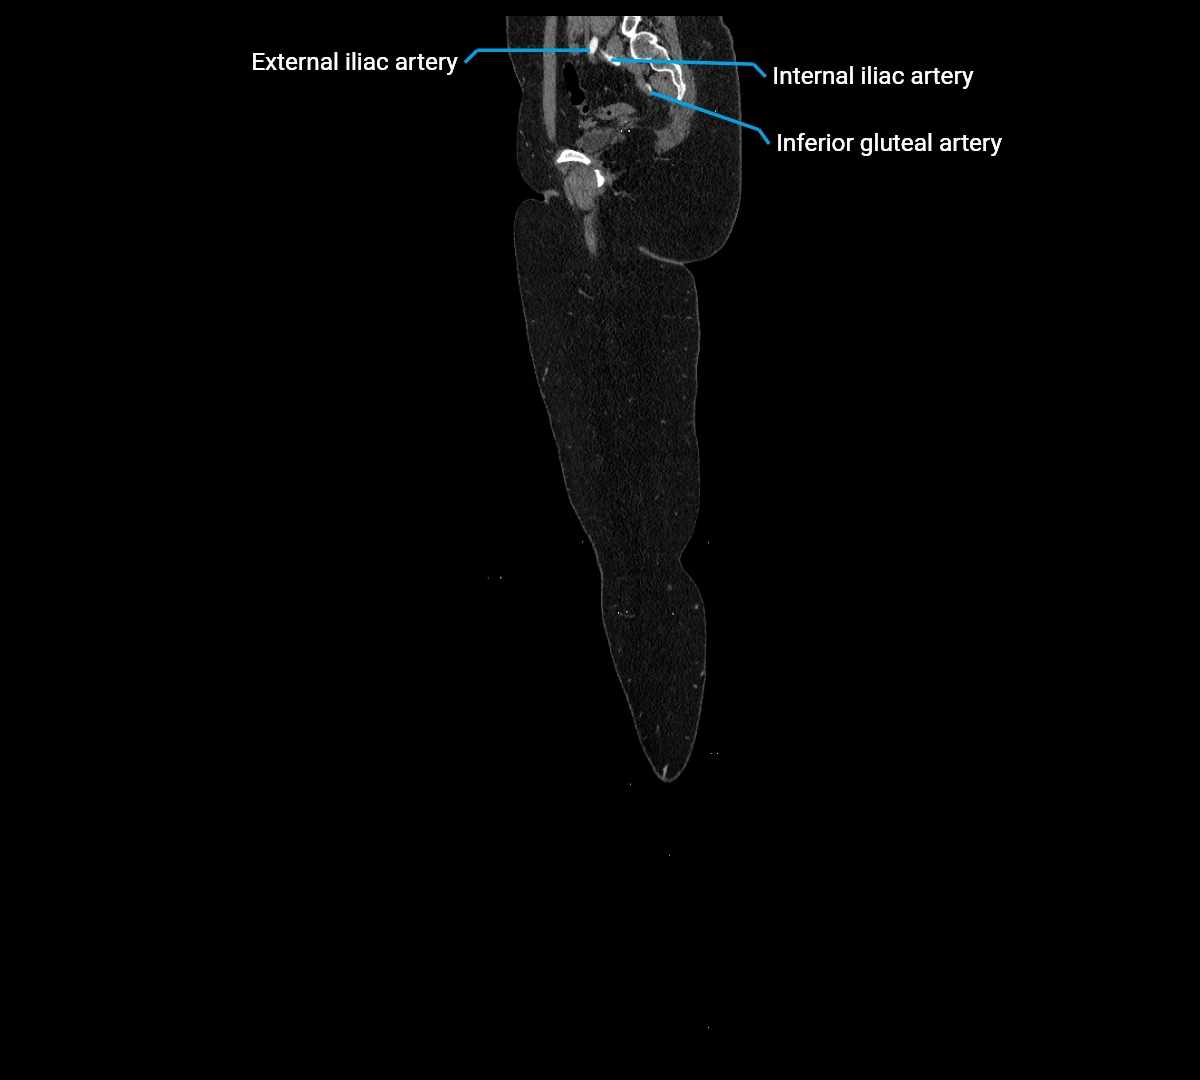

MRI images

image